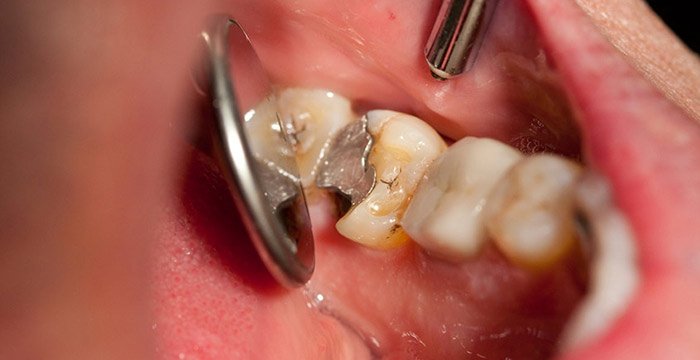

Клинический осмотр в стоматологической практике – единственный способ правильно оценить состояние десен и опорных структур зуба. При первичном осмотре стоматолог или гигиенист проведет базовый осмотр периодонта, который займет всего несколько минут. Это обследование быстро определяет наличие гингивита или периодонтита.

Стоматолог или стоматолог-гигиенист использует специальный зонд (называемый пародонтальным зондом) и аккуратно и точно измеряет глубину проникновения на линии десен в различных местах рта. Зонд измеряет расстояние между линией десны и дном «кармана». На здоровых участках глубина зондирования составляет 3 мм или менее, но при наличии периодонтита глубина составляет 4 мм и более.

После этого краткого осмотра дальнейшие тесты проводятся только при наличии признаков периодонтита, т. е. повреждения структур, поддерживающих зуб.

Кроме того, в так называемой пародонтальной карте точно записывается высота челюстной кости (уровень прикрепления). Пародонтальная карта необходима для правильной диагностики периодонтита и планирования последующего лечения.

Рентгенологические исследования. Диагноз периодонтита можно подтвердить только при проведении рентгенологического исследования. Выбор рентгеновских снимков, необходимых для диагностики периодонтита, производится после клинического осмотра.